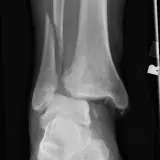

MSK Radiographs